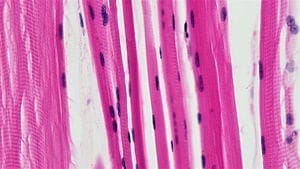

First histologic examination of the anterior scalene muscle. Machleder, Moll and Verity demonstrate microscopic transformation of the anterior scalene muscle in patients with TOS. They find an increase in the muscle fibers that cause slow-twitch, prolonged contraction, with concomitant loss of fast-twitch muscle fibers. This result suggest that the anterior scalene muscle has adapted to maintain higher levels of tension over a prolonged period. In 1990, Sanders publishes another study of scalene muscle structure. Patients with traumatic TOS had abnormal scalene muscles, but other neck muscles were normal. Sanders confirmed the change in muscle fiber types noted by Machleder, et al. However, Sanders also found a considerable increase in fibrous tissue in the abnormal scalene muscles. He suggested that this process resulted in a less flexible anterior scalene muscle, whose fibrous edges might “irritate nerves and produce neurologic symptoms, particularly in persons with anatomic predispositions to TOS.”